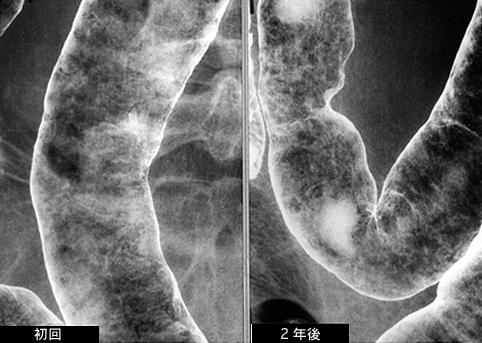

症例提示(所在地,施設名等): 東京都・ 国立がんセンター中央病院と九州がんセンターの共同作成

症例登録日 2005/03/30

画像ID:8162

疾患(病理主体)の分類炎症性・潰瘍性疾患/消化管アミロイドーシス

部位(臓器別)大腸/横行

検査方法X-P